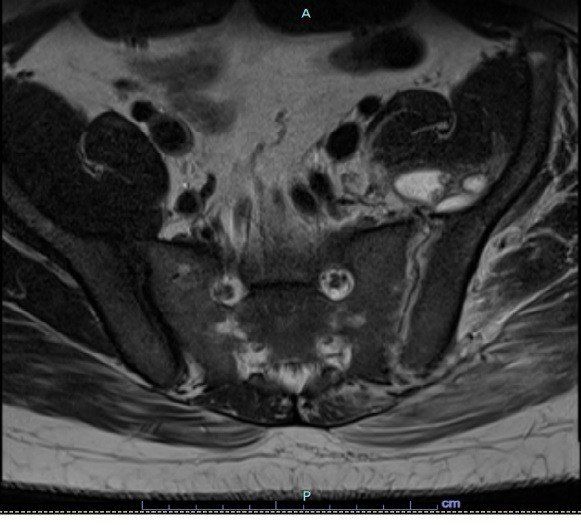

RM Coluna Lombo-sacra - Axial t1 com contraste: Sinais de sinovite associada a coleções inflamatórias com derrame articular com realce pós contraste. Estes achados estão frequentemente associados com artrite séptica da articulação sacro-ilíaca esquerda com abscessos junto aos grupamentos musculares adjacentes.

• Ressonância Magnética

Sensivel e mais especifico para dano cartilaginoso inicial

T1: baixo sinal em dentro do osso subcodral;

T2: edema perissinovial;

C+ (Gd): realce sinovial..